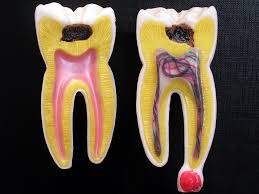

치아의 구조입니다.

치아의 가장 밖은

법랑질(Enamel)이라고 부르는

뼈만큼 단단한 부분이 있고,

그 안쪽에는

상아질(Dentin)이라고 부르는

상아색의 무른 부분이 있습니다.

치아의 가장 안쪽에는

신경과 혈관의 다발이 존재하고

이를 치수라고 합니다.

(Tooth pulp)

충치, 외상등으로 치수에 염증이 생기는 것을

치수염이라고 부르고

신경치료가 필요할 만큼 심한 앞니통증이 생기면

비가역성치수염,

여기서 더 진행이 되면

앞니변색이 생기는

치수괴사까지 이르게 됩니다.

위 사진처럼 치수괴사에 이르면

뿌리끝에 염증이 생겨

잇몸뼈가 점점 흡수 됩니다.